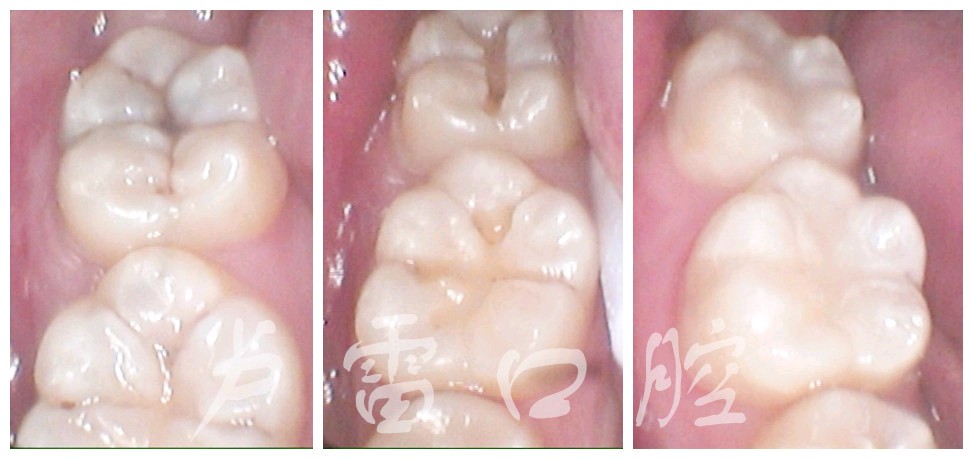

第一类是发生在所有的牙齿的窝沟内的龋齿所制备的洞,叫做Ⅰ类洞 (图一)。

图一

处理方案 : 1,树脂材料补牙。

分析:龋坏面积小,周围预留牙壁厚,补牙后材料不易脱落,牙齿也不易崩裂。补牙补牙最佳时期。